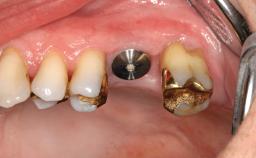

In this case, Arndt Happe describes how he achieved a stable outcome at 5 years by giving careful attention to the coronal aspect of the transmucosal area of the provisional, creating a slim emergence profile.

A healthy 31-year-old female patient presented with a failing maxillary left lateral incisor crown. The crown regularly loosened, and the remaining tooth was neither restorable nor rational to treat. The patient had a high smile line, a medium soft tissue biotype with a compromised mesial papilla (shorter than the contralateral one), and a horizontal scar in the buccal soft tissue as a result of past periapical surgery.